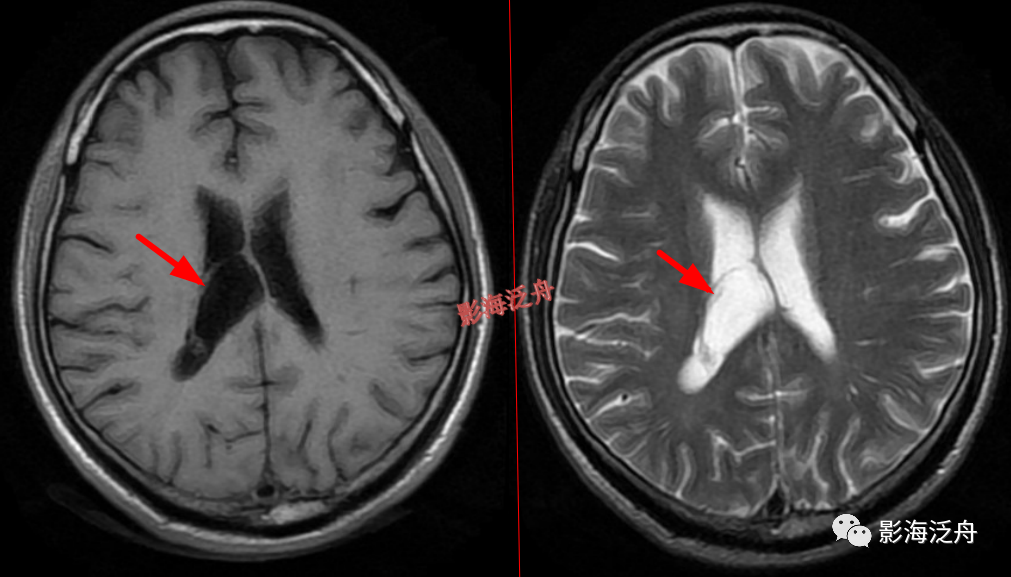

右侧侧脑室体部囊性占位(红箭),整体信号与脑脊液一致,病灶边缘部分显示,透明隔稍移位。

灰质移位,患者既往有癫痫病史。右侧侧脑室前角及左侧侧脑室后角可见异位的灰质结节(红箭),与大脑皮层下的灰质信号一致(绿箭),灰质异位患者多伴有癫痫症状。

透明隔缺如,我自己漏诊过的病例。上面有很多正常的图像可供对比观察。